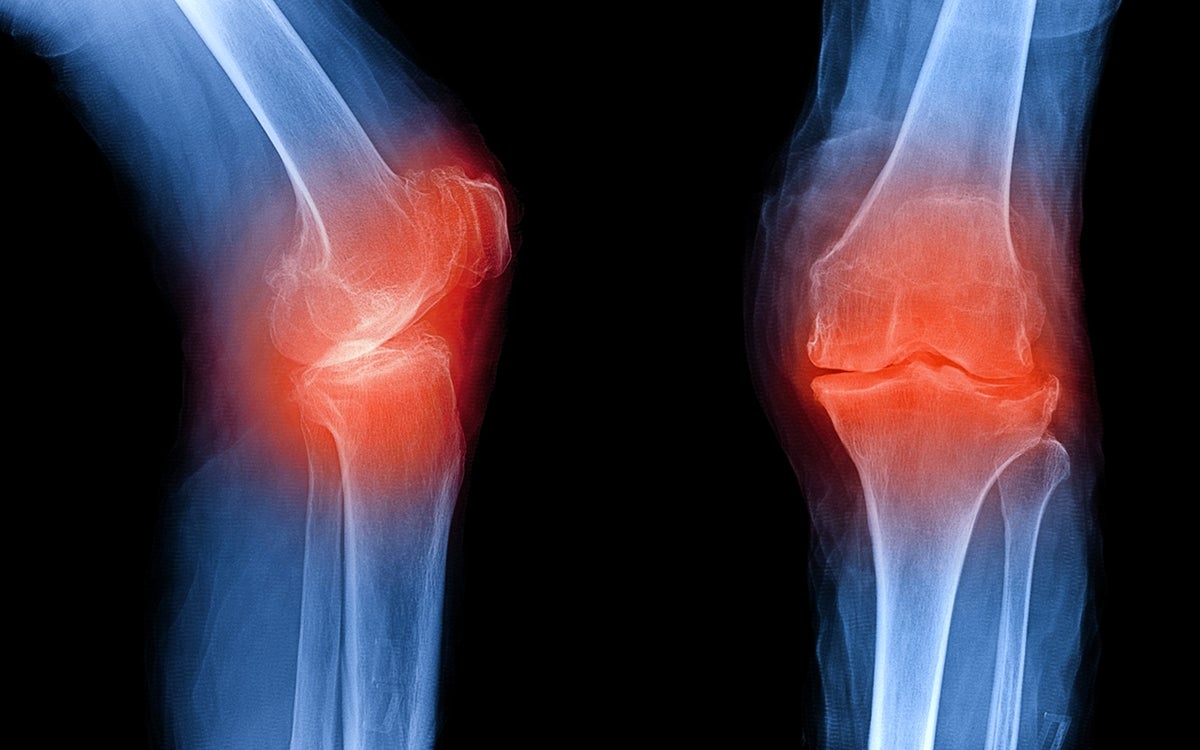

Laura Creemers (Regenerative Medicine Center) gaat onderzoeken hoe kraakbeen en tussenwervelschijven opnieuw kunnen aangroeien bij mensen met slijtage daaraan. Slijtage van kraakbeen leidt vaak tot artrose en slijtage van tussenwervelschijven tot chronische lage rugpijn. Laura gaat proberen beide weefsels aan te zetten tot regeneratie. “We willen de cellen ter plaatse aan het werk zetten. Dat doen we door de aanmaak van ontstekingsfactoren die voor weefselafbraak zorgen te remmen en door de aanmaak van groeifactoren te stimuleren. Dat kan door bepaalde genen uit te zetten met antisense nucleïnezuren (siRNA of miRNA) of door genen juist aan te zetten met mRNA. Ons project draait om de vraag: Hoe krijg je die moleculen de cel in?”, vertelt Laura.

Kraakbeen en tussenwervelschijven hebben amper doorbloeding en zijn heel compacte weefsels. Daarom geven de onderzoekers de moleculen dragers mee die opname in cellen makkelijker maken. Dit kunnen holle nanobolletjes zijn gemaakt van polymeer, of polymeren met een vertakte structuur die samen met het RNA een nanopartikel vormen. “Daarnaast kijken we ook naar natuurkundige manieren om het weefsel toegankelijker te maken”, gaat Laura verder. “We gebruiken daarvoor ultrasound, geluidsgolven met hoge frequenties die we niet kunnen horen. Ook onderzoeken we hoe de opname wordt beïnvloed door alle krachten die op het kraakbeen in een gewricht inwerken gedurende onze dagelijkse activiteiten.” Laura is coördinator van dit samenwerkingsproject van in totaal 4 miljoen euro voor 15 internationale promovendi. Zij brengt uiteindelijk alle kennis uit de deelonderzoeken bij elkaar om de aangroei van kraakbeen en tussenwervelschijven in patiënten mogelijk te maken.